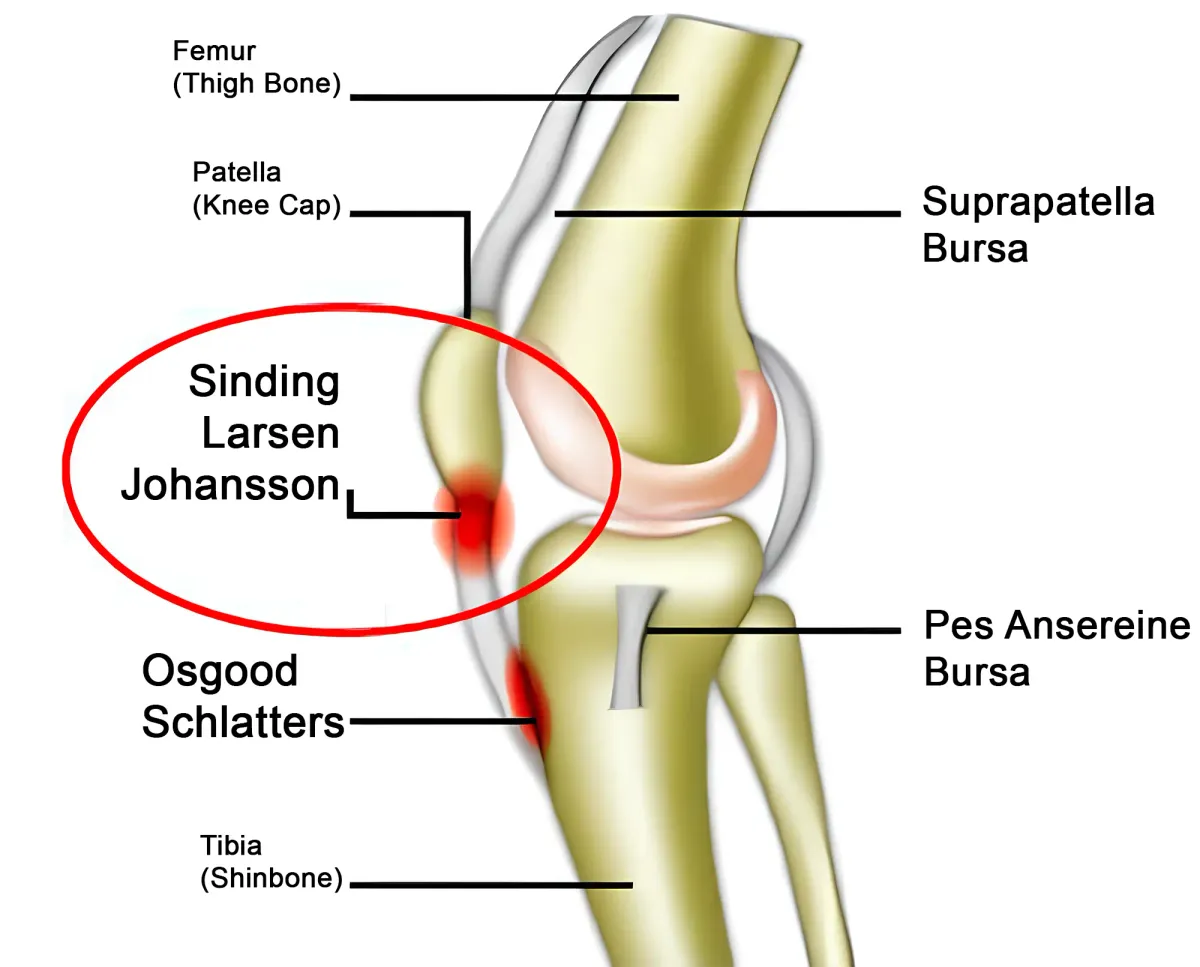

Ларсена йохансона

Ларсена йохансона 146 фото